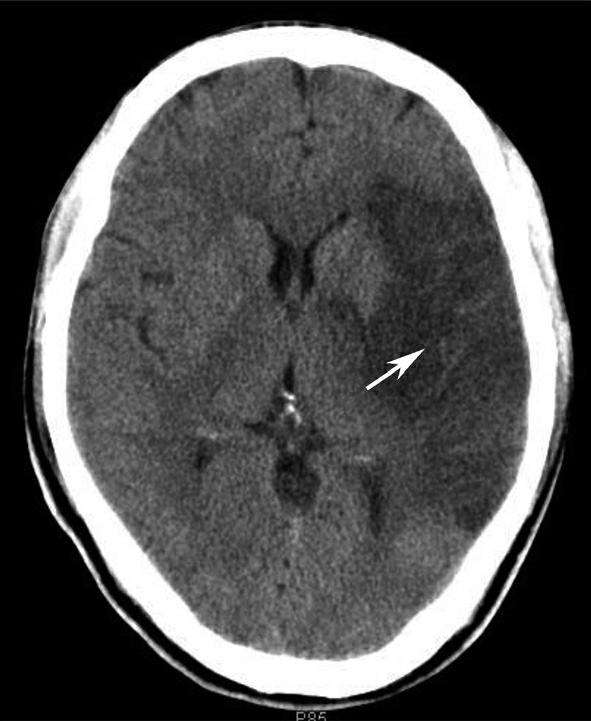

松果体、苍白球在成人期常出现钙化,属生理性钙化,一般无病理意义。需注意勿误诊为出血灶,尤其是单侧苍白球钙化时(图1-2-28)。

图1-2-28 苍白球生理性钙化

A.双侧苍白球对称性钙化,呈高密度影(箭);B.左侧苍白球钙化(箭),右侧苍白球钙化不明显